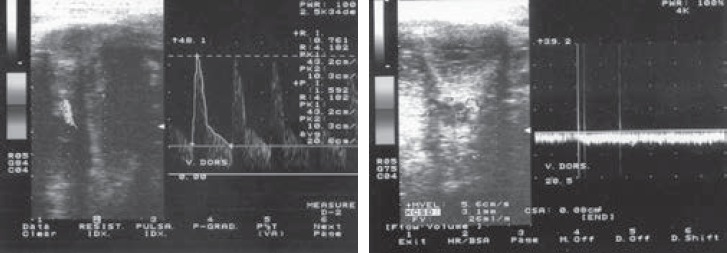

При ультразвуковой доплерографии простаты до лечения у больных всех трех групп определялось умеренное снижение Vmax от 5,2 до 5,8 см/с в субкапсулярных и парауретральных артериях, а также индексов периферического сопротивления (RI, PI). Через 12 недель после начала лечения при трансректальной доплерографии простаты отмечено увеличение Vmax в простате до 9,5 ± 4,1 см/с (норма — 4,5–11 см/с), особенно у больных 1-й группы. У больных 2-й и 3-й групп Vmax повышалась медленнее (см. табл. 3). Клинические примеры динамики доплерографических показателей у проходивших лечение больных представлены на рис. 1 и 2.

Рис. 1. Ультразвуковая доплерография полового члена больного М., 68 лет, с доброкачественной гиперплазией предстательной железы и артериогенной эректильной дисфункцией, получавшего комбинированную терапию в течение 12 недель (1-я группа): а — Vmax (пиковая систолическая скорость кровотока) в кавернозных артериях снижена до 6,8 см/c; б — после лечения Vmax увеличилась до 24 см/c

Рис. 2. Ультразвуковая доплерография полового члена больного А., 54 года, с доброкачественной гиперплазией предстательной железы и веногенной эректильной дисфункцией в стадии компенсации (2-я группа). Через 4 недели пиковая систолическая скорость кровотока — 11,2 см/c, проба Вальсальвы (+), в дорсальной вене — 26 мл/мин